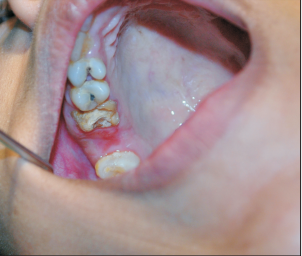

患者因龋坏拔除右上第二磨牙,术前X线片检查确定无根尖周疾病。拔牙术后三天进食出现鼻腔反流。

口内检查发现右上颌第二磨牙处可见4-6mm穿孔